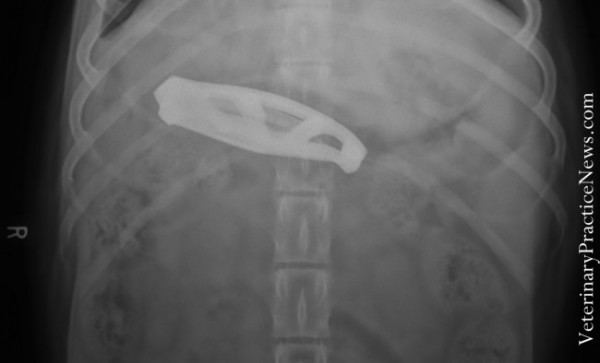

Ложка

Видимо собачка была настолько голодна, что съела ужин вместе с ложкой